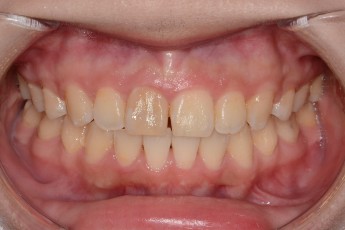

BEFORE & AFTER

- 덧니교정